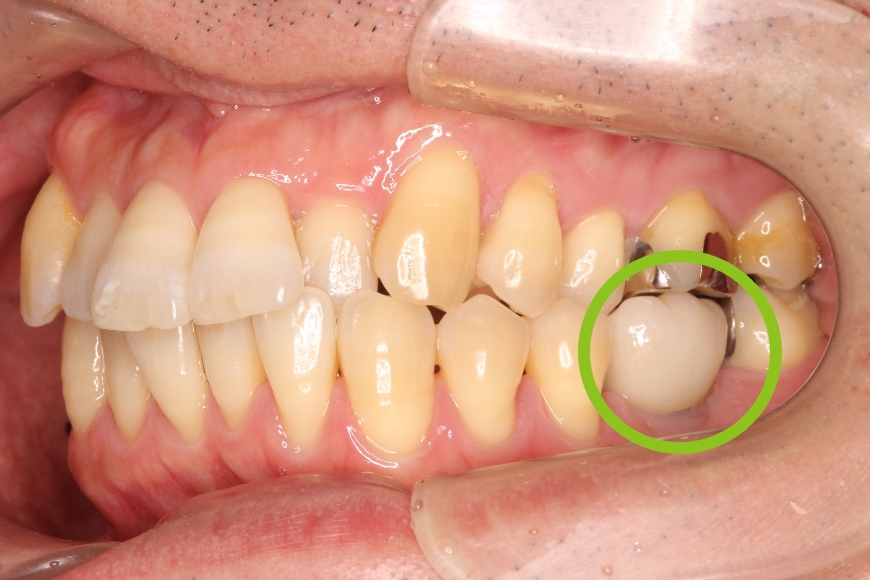

50代男性 左下の奥歯へのインプラント治療

治療内容 左下の奥歯が無く、食事がうまくできないことを主訴に来院されました。

歯が無い箇所にインプラント治療を行うことで、奥歯でしっかりと噛めるようになり、食事がおいしくなったとのことです。

治療期間・回数 治療期間:約3ヶ月

通院回数:5回程度

治療費用(総額)

440,000

(時期や手法により異なる場合があります。)